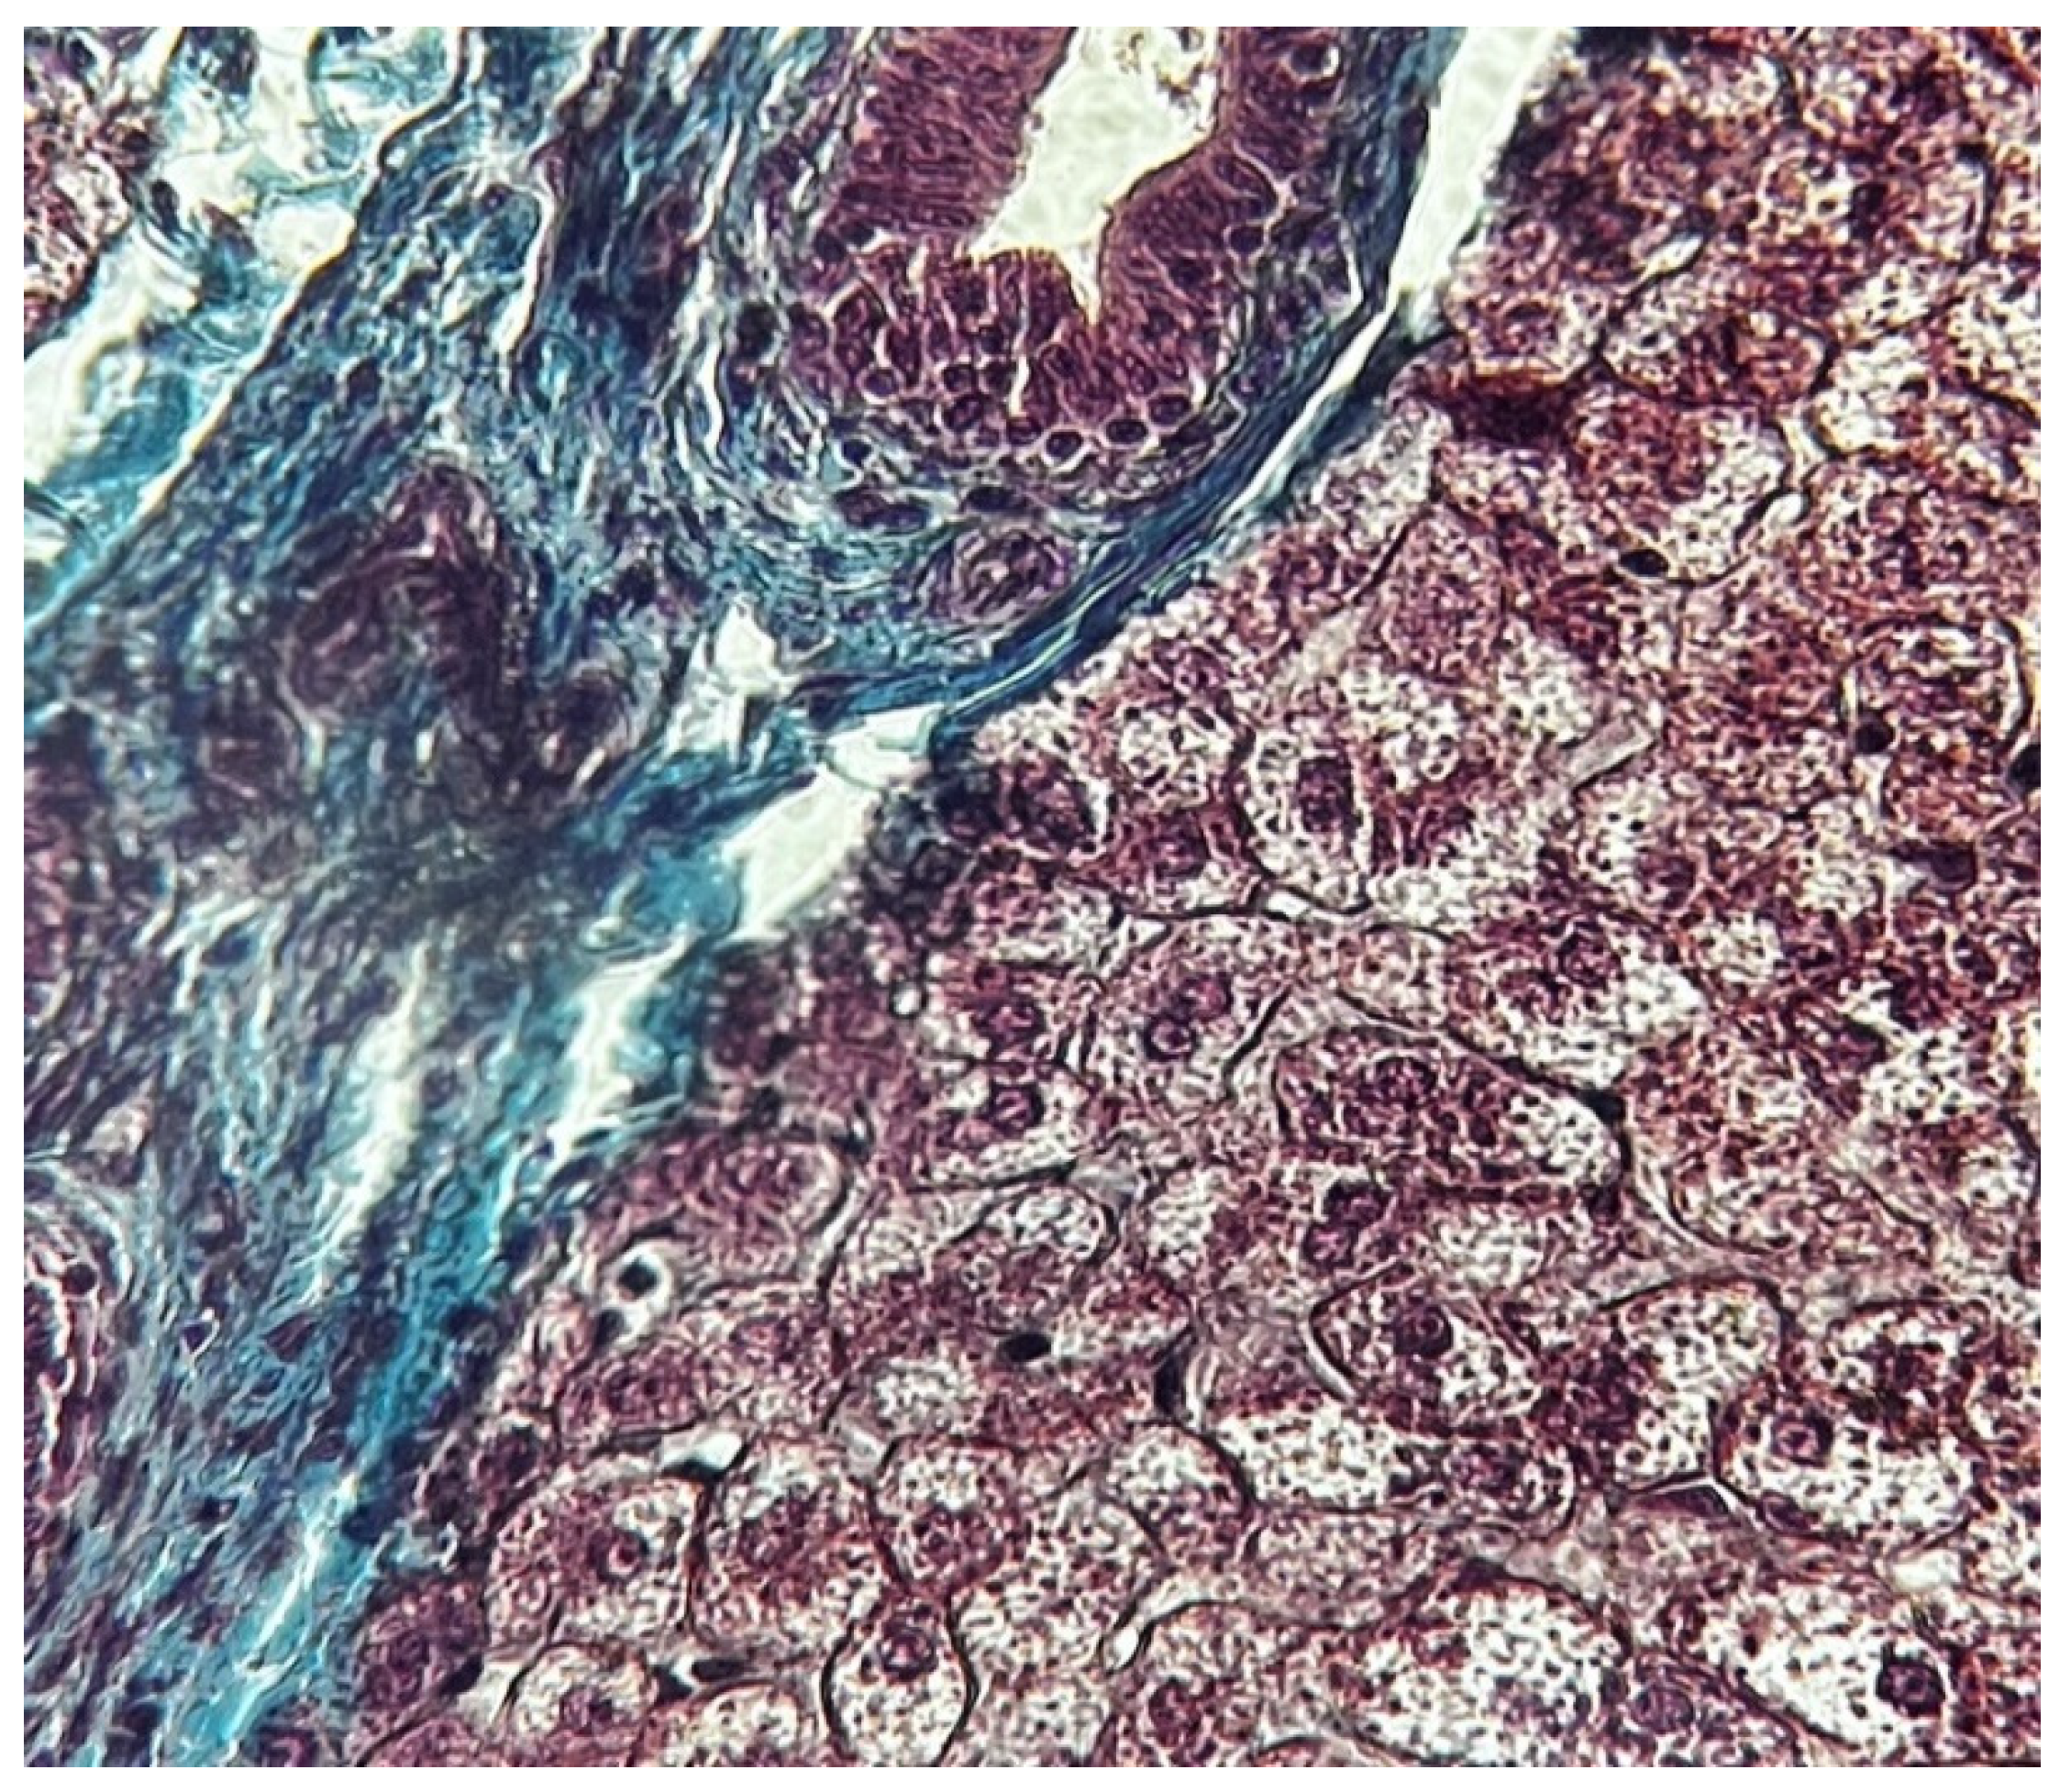

- Zone I is considered to be the periportal region of hepatocytes and are the best perfused and first to regenerate due to their proximity to oxygenated blood and nutrients. Implication in oxidative metabolisms.

- Zone II is defined as the pericentral region of the hepatocytes.

- Zone III has the lowest perfusion due to its distance from the portal triad. Implication role in detoxification.